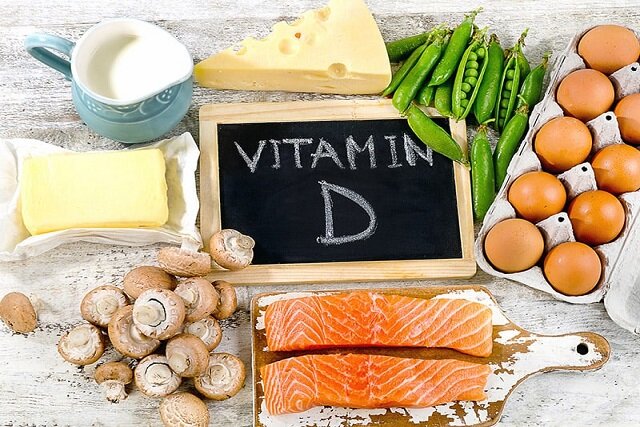

ویتامین D؛ ویتامینی برای حال خوب ذهن و بدن

آفتاب نیوز : ویتامین D که بیشتر با نقش آن در تقویت استخوان ها جذب کلسیم و حمایت از سیستم ایمنی شناخته می شود اکنون در کانون توجه پژوهشگران سلامت روان قرار گرفته است. نتایج تحقیقات جدید نشان می دهد…

هشدار درباره مصرف بی رویه ی ویتامین D

آفتاب نیوز : دکتر «آصف احمد» در ویدئویی گفت افراد بسیار زیادی را دیده است که دز بسیار بالای ویتامین D را مصرف می کنند که می تواند باعث ریتم غیرطبیعی قلب نارسایی کلیه و درد استخوان شود. در حال…

آفتاب نیوز : متخصص تغذیه یلنا تیخومیروا سه ویتامین را که نقش کلیدی در روند کاهش وزن دارند نام برد. به گفته ی وی سهم مهمی در کاهش وزن را ویتامین دی و سپس ویتامین های بی و سی بازی…